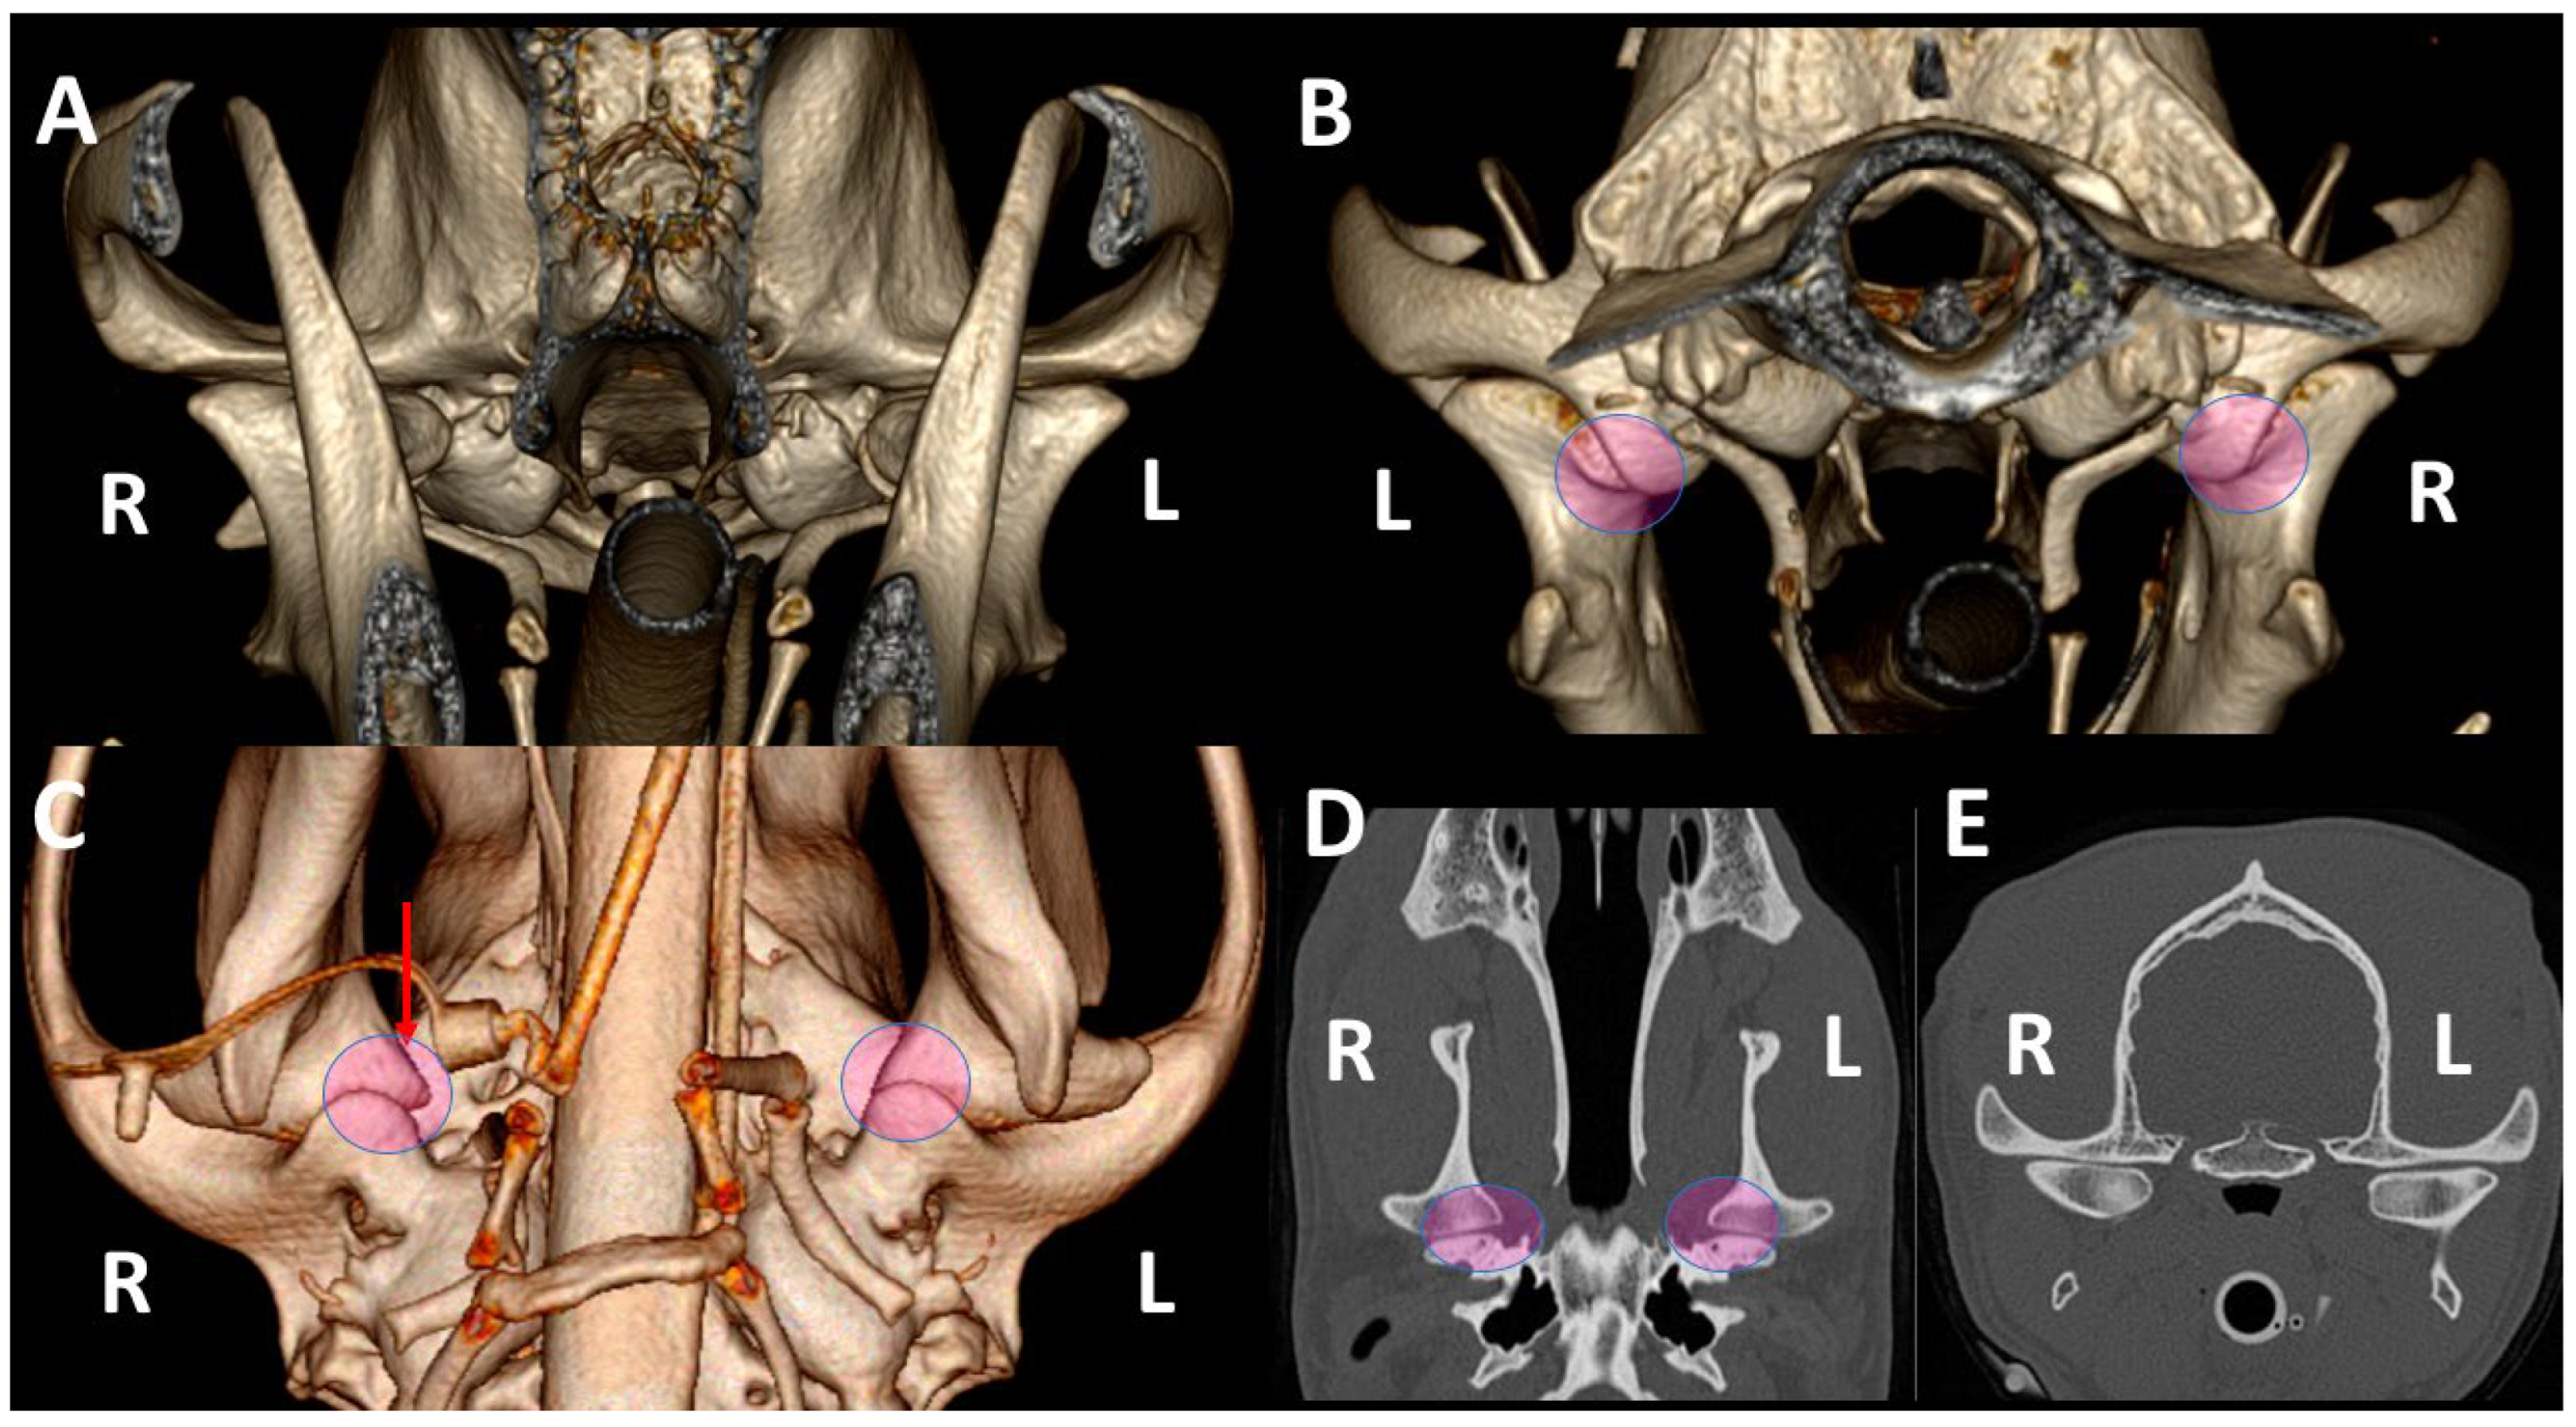

3.1. A Detailed Description of the Bone Anatomy of TMJ Using 3DVR Images

3.2. Comparison by 3DVR of TMJs in Each Dog, According to Skull Type and Age

3.3. A Detailed Assessment of Each TMJ Comparing 3DVR Images with the Three Standard CT Planes